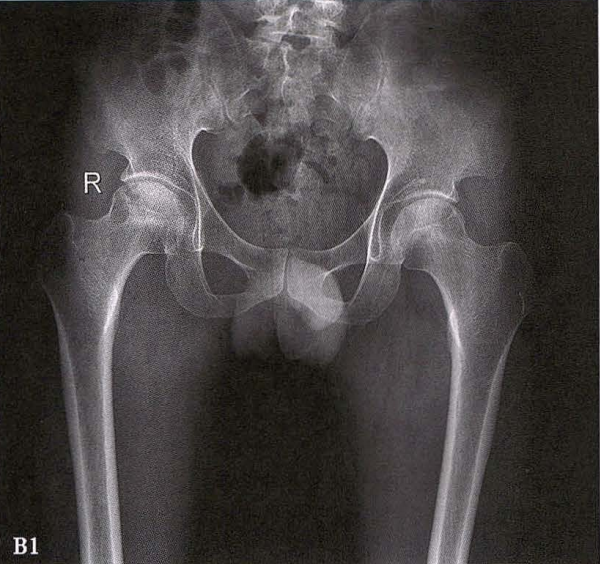

A.男性,71岁,双侧股骨头坏死,右侧Ⅰ期、左侧Ⅲ期。X线片示双侧股骨头形态可,右股骨头未见明显密度改变,左股骨头关节面下见局限性骨密度减低及增高区(A1)。MRI(T2加权像)示右股骨头内双线征,左侧不规则形混杂信号,坏死区远端骨髓水肿(A2、A3)。

B.男性,31岁,双侧股骨头坏死,双侧均为Ⅲ期。X线片示双侧股骨头密度不均、股骨头稍变扁(B1)。MRI(T1加权像)示股骨头内多发不规则信号带(B2),股骨头内凸向大转子的双线征(白色箭)和软骨下骨骨折(白色三角)。